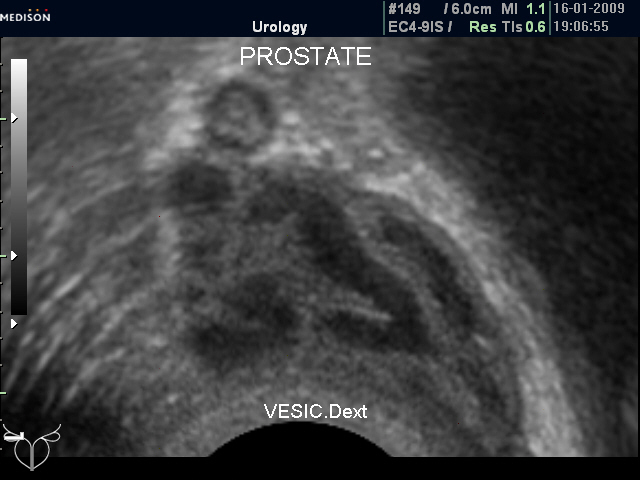

Нормальные семенные пузырьки при ТА и ТР УЗИ (фото 1 и 2).

Нормальные СП (ТР УЗИ)